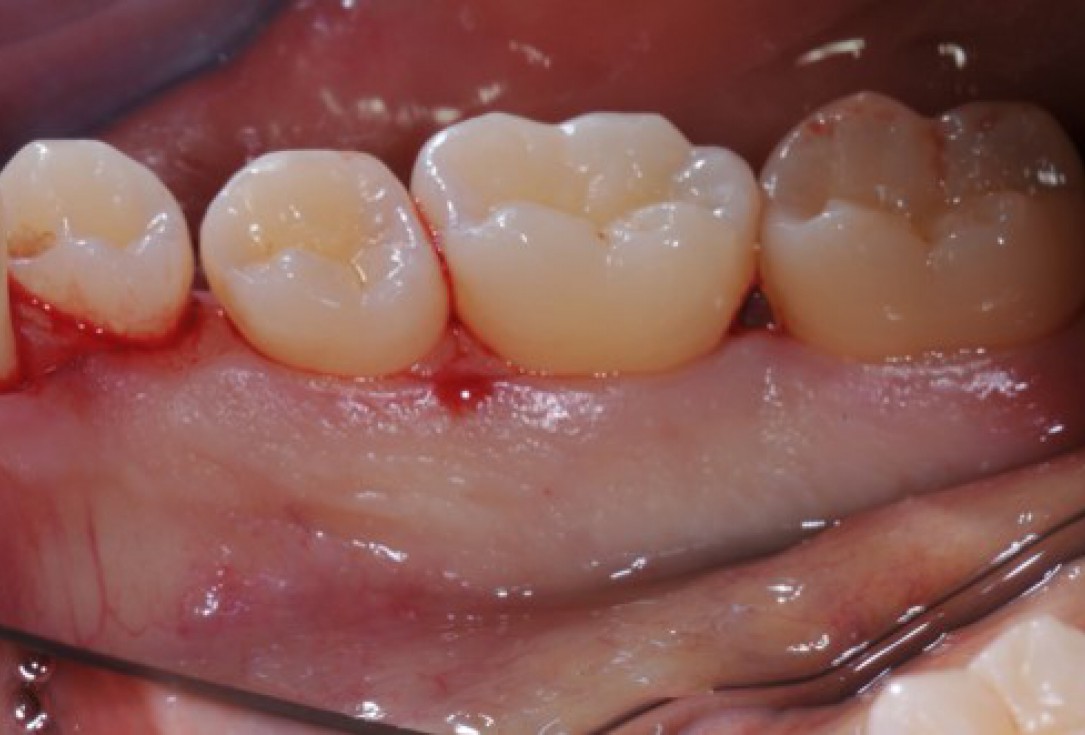

15/22 - Clinical situation 12 months post-operative. Buccal view.

Deep intrabony defects treated using Straumann® Emdogain® - Dr. M. Stefanini